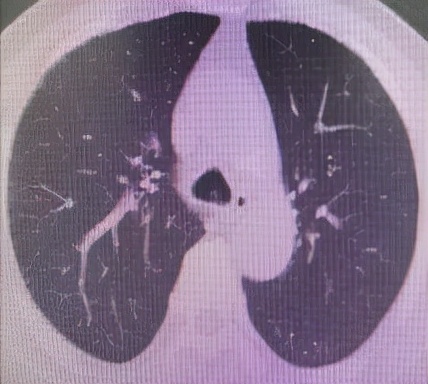

肺 部 C T (削瘤前)

于世寰主任介绍到,患者气管分叉处占位病变面积较大,已累及左、右主支气管,从肺CT影像上判断隆突区病变导致左主支气管狭窄约70-80%左右、右主支气管狭窄约50-60%左右,可操作空间十分有限,支气管镜介入治疗难度较大。隆突区占位病变已累及左右主支气管导致了呼吸困难已不适宜行外科手术治疗,必须通过支气管镜削瘤治疗来解除病人因气道梗阻导致的呼吸困难。支气管镜削瘤治疗与开胸外科手术相比,有痛苦小、创伤小、花费少、可重复性强、并发症少等优点。